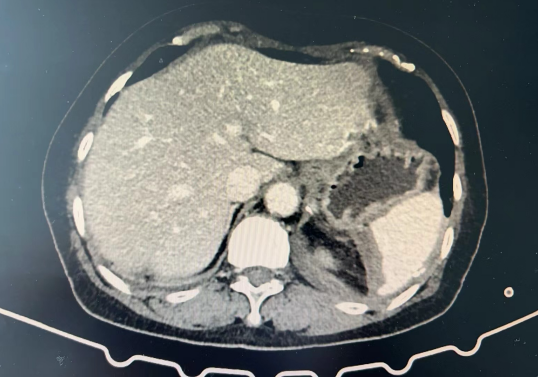

【学科技术】创新手术助力患者康复 —— 我院成功实施首例“腹腔镜脾部分切除术+胆囊切除术”